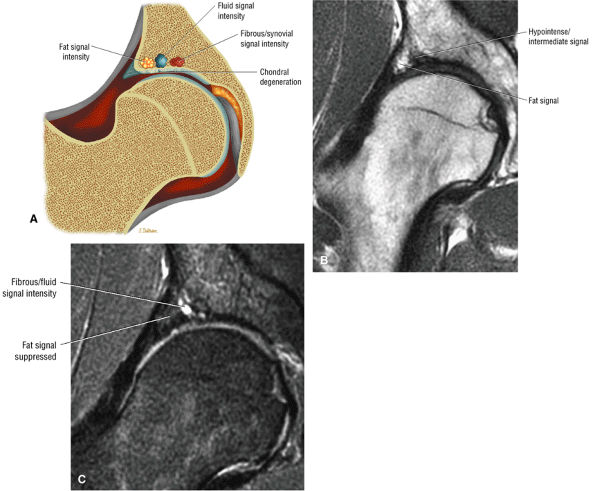

-

A defect, attenuation, or fissure in the normally intermediate-signal-intensity articular cartilage

A femoral “dysplastic bump” with normal marrow fat signal or a hyperintense signal and small hyperintense femoral head/neck cysts

A hypointense thickened hip capsule (iliofemoral ligament)